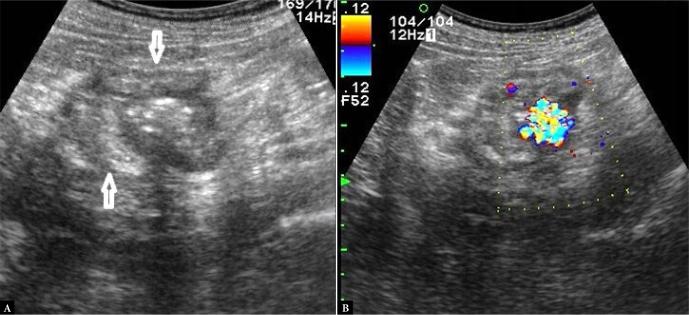

The aim of this paper is to present our experience in transabdominal ultrasonography of ileocecal valve lesions. The ileocecal valve, located in the central part of the ileocecal bowel segment, is rarely the primary site of disease processes. It is usually involved by pathologies in adjacent bowel segments. These are primarily infectious diseases such as yersiniosis, campylobacteriosis and salmonellosis. Typical location of Crohn's lesions also promotes valve involvement. The appearance of the lesions in these cases is characterized by a symmetrical submucosal thickening of the bowel involved over a longer segment. Non-malignant valvular hyperplasia is relatively commonly identified as lipomatosis, manifested by symmetrical enlargement and smooth outlines. However, valvular lipoma causing an asymmetrical hyperechoic bulge is a rare finding. ileocecal valve lipomatosis or lipoma should not be misdiagnosed as a lipoma of the cecoascending part of the colon and, the other way round, a right colonic lipoma should not be mistaken for a fatty valve. Polyps on the ileocecal valve, although sometimes detected, were not identified in our material. Adenocarcinoma, which is found in the cecum in approximately ¼ of cases, is the most common malignancy, followed by neuroendocrine tumor and, rarely, lymphoma. In three cases of malignant involvement of the ileocecal valve, we observed irregular hypoechoic thickening with complete loss of wall stratification, with the lesions causing symptoms of small bowel obstruction in two of these cases. The nearly forgotten ileocecal valve syndrome, also known as Bauhin's ileocecal valve syndrome, characterized by intermittent right iliac fossa pain, is also briefly discussed. Transabdominal ultrasound can be used as an initial diagnostic tool in some of these pathologies.

本文旨在介绍我们在经腹超声检查回盲瓣病变方面的经验。回盲瓣位于回盲肠段的中部,很少是疾病过程的主要部位。它通常受相邻肠段病变的累及。这些病变主要是传染病,如耶尔森菌病、弯曲菌病和沙门菌病。克罗恩病病变的典型位置也会促使回盲瓣受累。在这些病例中,病变的表现特征为受累肠段较长范围的对称性黏膜下增厚。非恶性瓣膜增生相对常见的是脂肪瘤病,表现为对称性增大且轮廓光滑。然而,导致不对称高回声隆起的瓣膜脂肪瘤是罕见发现。回盲瓣脂肪瘤病或脂肪瘤不应误诊为结肠升结肠部的脂肪瘤,反之,右半结肠脂肪瘤也不应误认为是脂肪性瓣膜。回盲瓣上的息肉虽然有时能检测到,但在我们的资料中未发现。腺癌在盲肠中约四分之一的病例中被发现,是最常见的恶性肿瘤,其次是神经内分泌肿瘤,很少见的是淋巴瘤。在三例回盲瓣恶性受累病例中,我们观察到不规则低回声增厚,壁分层完全消失,其中两例病变导致小肠梗阻症状。还简要讨论了几乎被遗忘的回盲瓣综合征,也称为鲍欣回盲瓣综合征,其特征为间歇性右下腹疼痛。经腹超声可作为其中一些病变的初步诊断工具。